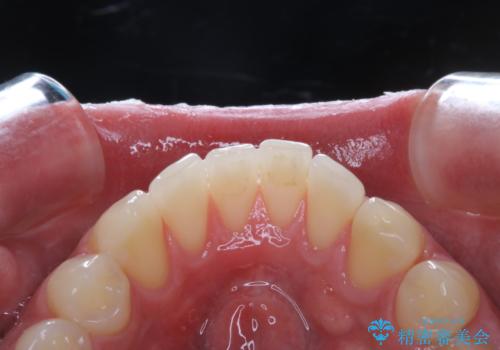

親知らずを抜いて1週間後にPMTC 歯のクリーニング

抜歯後は多少出血したり、違和感や痛みを感じたりすることがあります。そのため親知らずを抜いたり、外科的な処置をするといつも通りの歯磨きがしづらくなります。また、傷口の周りが心配で、歯ブラシをするのが怖くなるものです。抜歯後落ち着いたら、歯科医院にて専門の機械を使用しクリーニングをすることがおすすめです。抜歯前や後にPMTCを行うことで、お口の中の健康維持につながり、その後の感染・腫れ・口臭予防などになります。

親知らず抜歯後正常に治癒が進んでいれば1週間後から可能です。